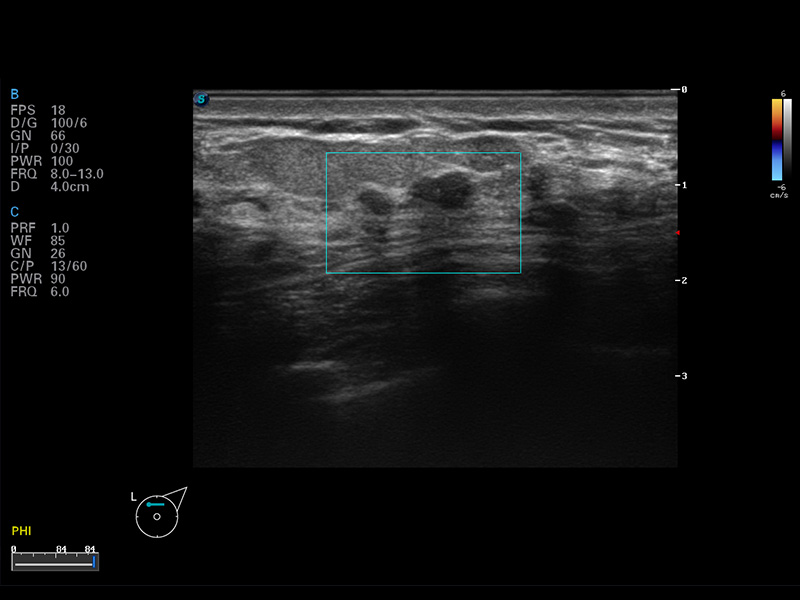

S8 EXP便携式彩色多普勒超声诊断仪是美狮贵宾会官网研发的高端全身应用型便携彩超。高通道的VIS平台融合可视化(Visual)、智能化(Intelligent)和人性化(Smart)的特点,配以美狮贵宾会官网自主研发生产的探头大家族,使您能够快速、准确的获得病人信息,提高工作效率的同时减轻疲劳。

谐波成像

空间复合成像